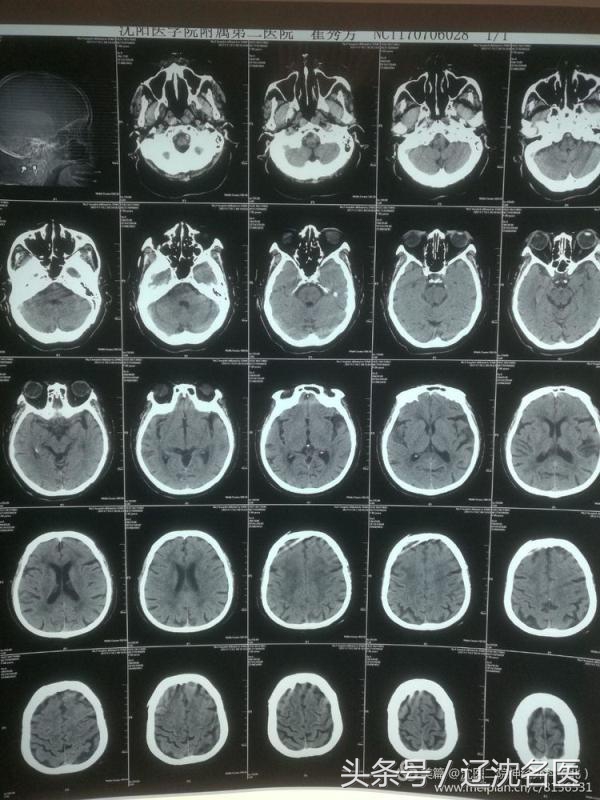

女患刘某,83岁,神志不清4个多小时。患者送到急诊室时已经昏迷,大小便*禁失**,双侧瞳孔不规则,四肢瘫,随时都有呼吸、心脏骤停的危险。情况十分危急,急诊科立即为患者开通绿色通道。头CT检查结果未见出血。神经外科孙冬弢主任会诊后诊断为急性脑梗塞,脑干梗塞。

此时的患者心率上升到125次/分,血压190/115mmhg。因患者病情危重,静脉溶栓已经超过了时限,如果采用血管介入机械取栓,尚有一线希望。主治医生赵云东在争得家属同意后,立即将患者推到导管室行脑血管造影检查,结果发现患者基底动脉闭塞。